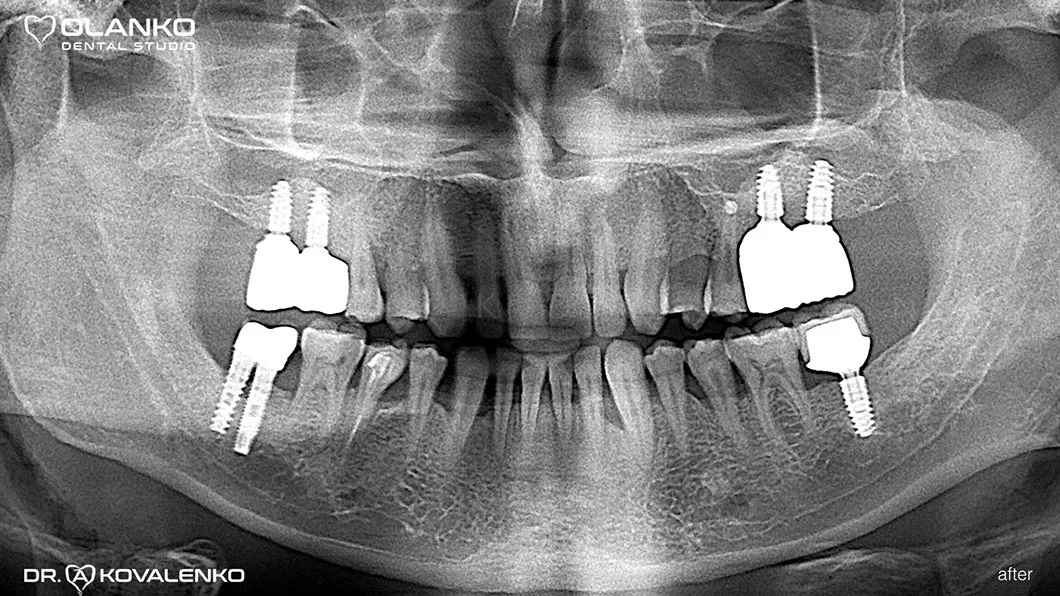

Лечение: операция костной пластики на верхней челюсти (двухсторонний синус-лифтинг). Установка 4-х зубных имплантатов на верхней челюсти и один зубной имплантат на нижней челюсти. Пластика мягких тканей в области имплантатов.

Керамические коронки зафиксированы на имплантаты

До и После:

после